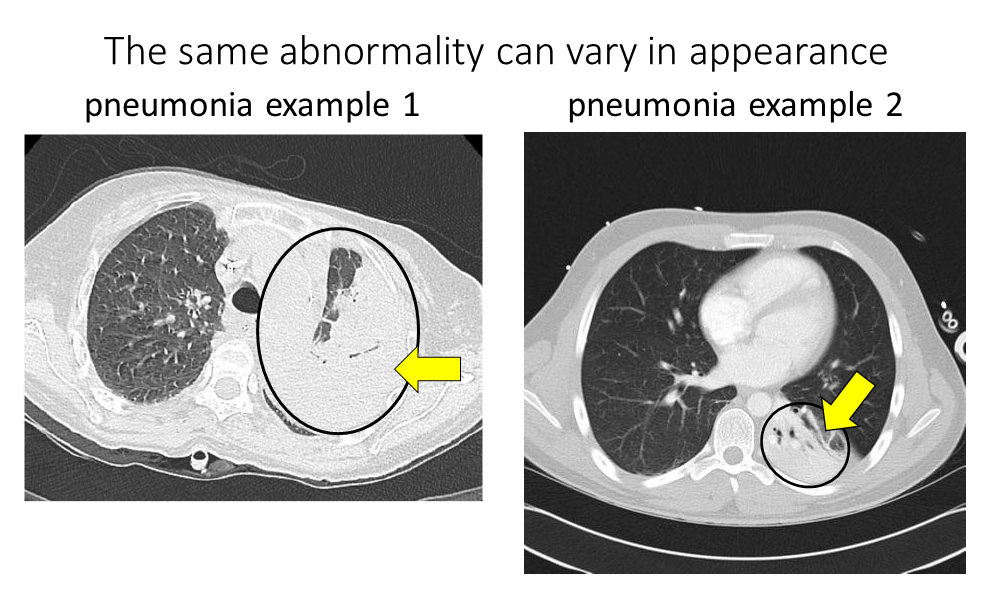

Challenge 6: The same abnormality can vary in appearance. For example, the same abnormality will look different depending on severity, such as the pneumonia scans below where the scan on the left has an entire lung “whited out” by pneumonia while the scan on the right contains only a smaller part of the lung “whited out” by pneumonia:

Modified from these original images: pneumonia example 1 Kalpana Bansal. Pneumonia example 2 Radiopaedia